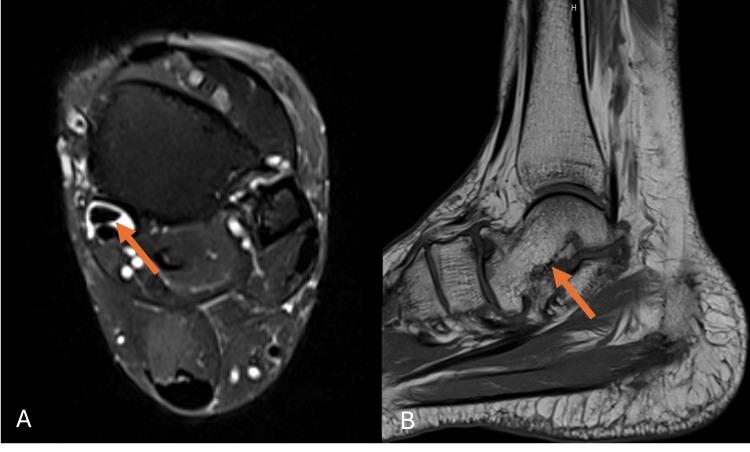

Congenital Absence of the Navicular Bone: A Rare Cause of Adult-Acquired Flatfoot and Posterior Tibial Tendon Dysfunction.

The navicular bone is critical for foot biomechanics, stabilizing the midfoot through its articulation with the talus and cuneiform bones. Variations, including accessory ossicles, hypoplasia, and complete absence, can lead to altered foot function. We present the case of a 58-year-old female patient who experienced persistent left foot pain. Imaging revealed the congenital absence of the navicular bone, resulting in altered biomechanics, midfoot instability, flatfoot deformity, and secondary degenerative changes. Posterior tibial tendon dysfunction (PTTD), a leading cause of adult-acquired flatfoot, is exacerbated by navicular anomalies. Advanced imaging plays a critical role in diagnosis, with treatment ranging from conservative management to surgery, depending on severity.